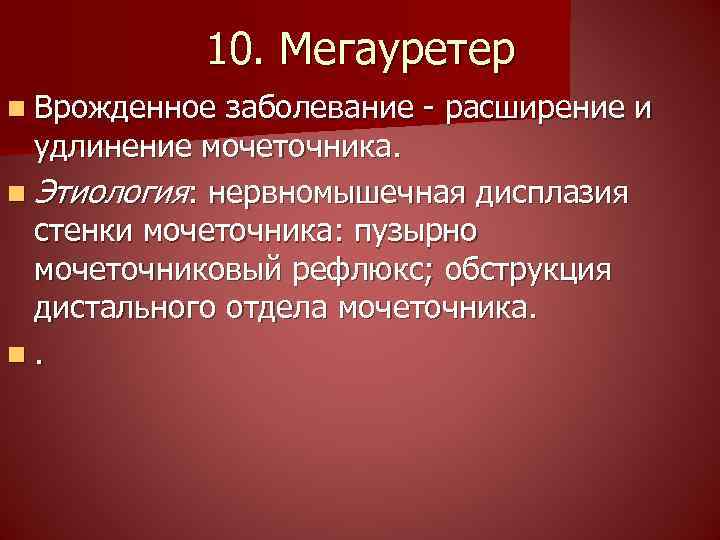

Рефлюксирующий мегауретер: Визуализация и медицинские изображения

Раздел: Фотопуть к знанию